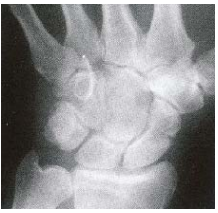

(A)大多角骨(Trapezium bone) (B)小多角骨(Trapezoid bone) (C)舟狀骨(Scaphoid bone) (D)月狀骨(Lunate bone)